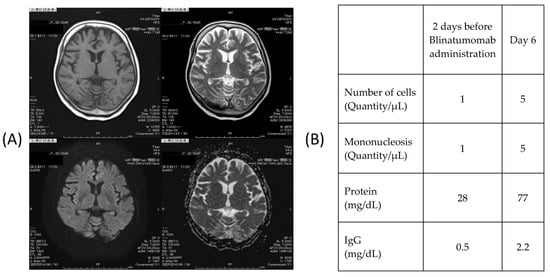

After the onset of dysgraphia, brain magnetic resonance imaging (MRI) and a cerebrospinal fluid (CSF) test were performed but no obvious abnormality was detected. The CSF examination uncovered an increase in CSF protein levels, which indicated the possible development of encephalitis or meningitis despite no formal diagnosis (Figure 3).

Figure 3.

(A) Head magnetic resonance imaging. Findings: There is no obvious abnormal signal area in the brain parenchyma. There was no abnormal contrast area in the Gd. The pituitary gland was normal in size. The high T1WI signal in the posterior lobe was also maintained. (B) Cerebrospinal fluid test. The spinal fluid examination showed an increase in cerebrospinal fluid protein, so it is possible that some kind of encephalitis or meningitis had occurred, although it was not diagnosed.